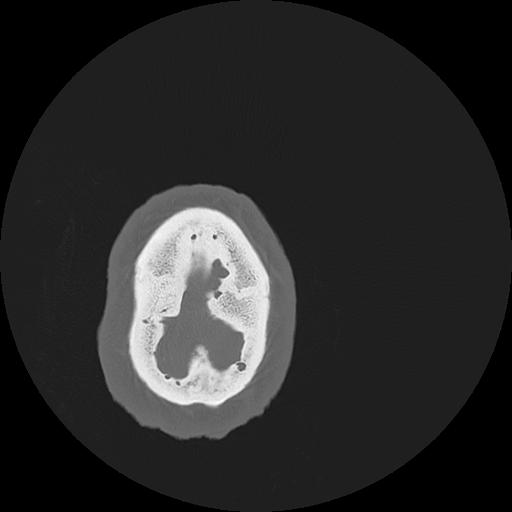

7 HUESO,,Vol,0.5,HUESO,,